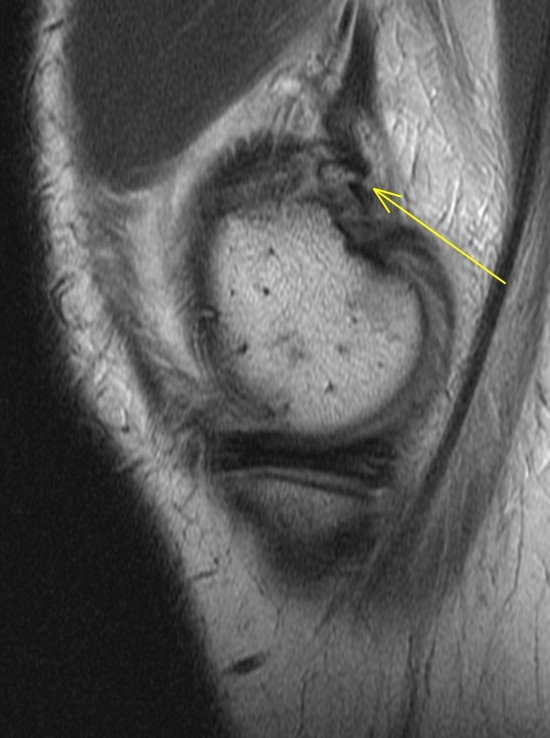

14 y/o tackled from the side after blocking a field goal in American football

The adductor magnus insertion is avulsed and there is fluid within the physis consistent with a SH injury (probable type 2 although its a bit tough to say whether the fragment was metaphyseal or epiphyseal). There was also subperiosteal blood laterally. Orthopedist saw an ossicle on plain films. Alignment good and no ACL or meniscus so he will be put in a brace and treated conservatively. Father asked if he could play in 3 weeks. I said nope.

Avulsion fracture of the adductor magnus insertion